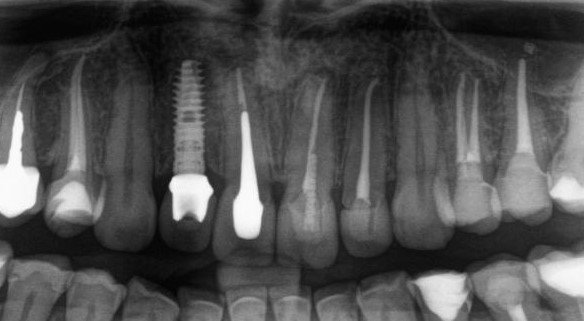

Вот почему при любом методе остеопластики, будь то вертикальная или горизонтальная, аутотрансплантация или НКР, важно создать как можно большую площадь контакта между костью челюсти и графтом. Особенно это касается ситуаций, когда вы сочетаете остеопластику с установкой имплантатов — они существенно уменьшают площадь контакта графта с костной тканью:

Кроме того, создавая костную рану, мы стимулируем стимулируем остеокластическую активность, столь необходимую для запуска регенерации. И получаем хороший результат наращивания костной ткани: